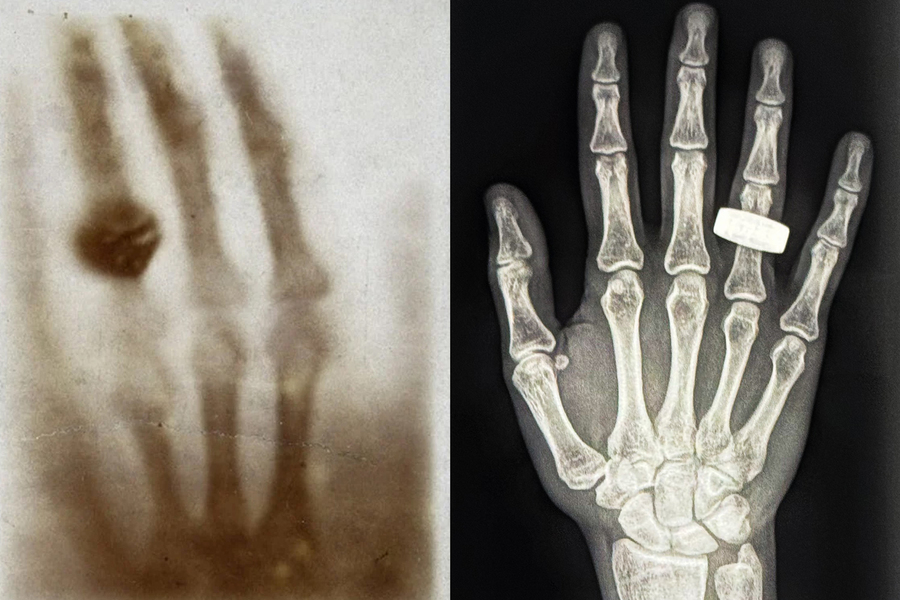

MIT’s Lonnie Petersen on the first medical X-ray taken in space: Performed in microgravity, 200 miles above the Earth’s surface, the imaging procedure could help keep astronauts safe and healthy on long-term missions.